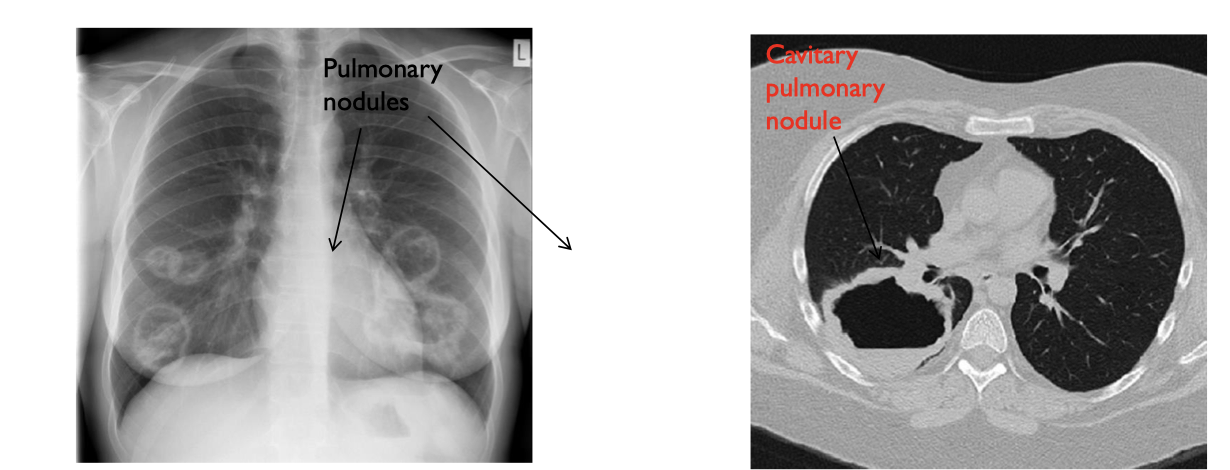

what type of AAV would this person be struggling with?

GPA. GPA is more frequently associated with pulmonary nodules than is MPA